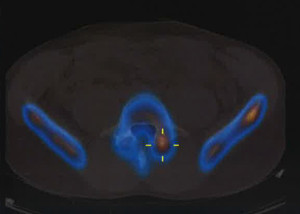

SPECT-EspondilolisisSPECT-EspondilolisisLa espondilolisis se define como un defecto óseo en la pars interarticular del arco vertebral. Se presenta una debilidad o fractura en uno de los puentes óseos que conecta las articulaciones facetarias. Este defecto o bien puede ser asintomático o asociado con un significativo dolor lumbar. Esta condición está presente en hasta un 6% de la población, sin embargo sólo el 10-15% de las personas desarrollará síntomas. Aunque la etiología de esta lesión todavía no está clara, se ha demostrado que existen factores de riesgo hereditarios y adquiridos, con una mayor prevalencia en hombres y atletas que participan en ciertos deportes de alto riesgo. La espondilolisis es, en efecto, una causa común de dolor lumbar en los atletas preadolescentes y adolescentes y en particular presenta un problema clínico en esta población. Ocurre con mayor frecuencia en las personas que participan en algunas actividades que parecen suponer un estrés inusual en su columna lumbar.

TAC-espondilolisisTAC-espondilolisisGimnastas, practicantes de fútbol americano, levantadores de pesas, luchadores, bailarines y conductores son las personas más comúnmente afectadas. Por ello, en estos casos debe considerarse la posibilidad de una fractura por sobrecarga de la pars interarticular que puede dar lugar a una espondilolisis y/o espondilolistesis.

Desafortunadamente, se realizan diagnósticos erróneos de espondilólisis. Un factor de complicación en las primeras etapas de la enfermedad que conduce a un diagnóstico erróneo es el hecho de que las radiografías simples, incluso las oblicuas, pueden no ser útiles en la etapa de fractura por sobrecarga. Otras técnicas de imagen, como la gammagrafía ósea, posiblemente, la resonancia magnética o Tomografía computarizada de emisión monofotónica (SPECT) deben ser utilizadas al inicio del proceso de diagnóstico. En el ámbito de la atención primaria, el diagnóstico precoz de elemento de participación posterior relacionado con el dolor lumbar, ya sea en la etapa de la fractura por sobrecarga del pars o por espondilolisis temprana, puede prevenir la progresión de la enfermedad y evitar la necesidad de una intervención quirúrgica.